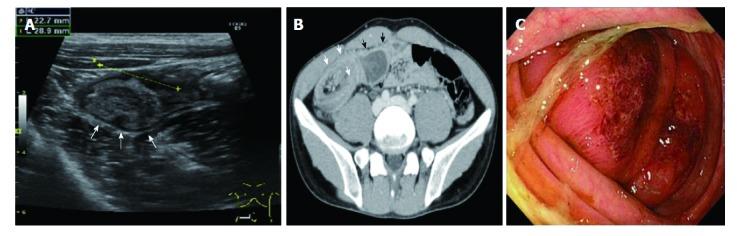

A 27-year-old man with recurrent right lower quadrant pain was admitted to our hospital. Ultrasonography and computed tomography examination of the abdomen revealed a target sign in the ascending colon, which was compatible with the diagnosis of cecal intussusception. The intussusception was spontaneously resolved at that time, but it relapsed 6 mo later. The patient underwent a successful colonoscopic disinvagination; there was no evidence of neoplastic or inflammatory lesions in the colon and terminal ileum. The patient underwent laparoscopic surgery for recurring cecal intussusception. During laparoscopy, we observed an unfixed cecum on the posterior peritoneum (i.e. a mobile cecum). Thus, we performed laparoscopic appendectomy and cecopexy with a lateral peritoneal flap using a barbed wound suture device. The patient's post-operative course was uneventful, and he continued to do well without recurrence at 10 mo after surgery. Laparoscopic cecopexy using a barbed wound suture device is a simple and reliable procedure that can be the treatment of choice for recurrent cecal intussusception associated with a mobile cecum.

一位 27 岁男性,反复右下腹痛,就诊于我院。腹部超声和 CT 检查提示升结肠靶环征,符合盲肠套叠诊断。当时套叠自行复位,但 6 个月后再次复发。患者接受了成功的结肠镜下复位术,结肠镜检查未见结肠和末端回肠有肿瘤或炎症性病变。患者因反复发生的盲肠套叠行腹腔镜手术。术中观察到后腹膜上的盲肠不固定(即盲肠活动度大),遂使用带倒刺缝线的缝合装置行腹腔镜阑尾切除术和侧腹膜瓣盲肠固定术。患者术后恢复顺利,无并发症,术后 10 个月无复发,恢复良好。使用带倒刺缝线的缝合装置行腹腔镜盲肠固定术是一种简单可靠的术式,对于与盲肠活动度大相关的复发性盲肠套叠,可作为首选治疗方法。